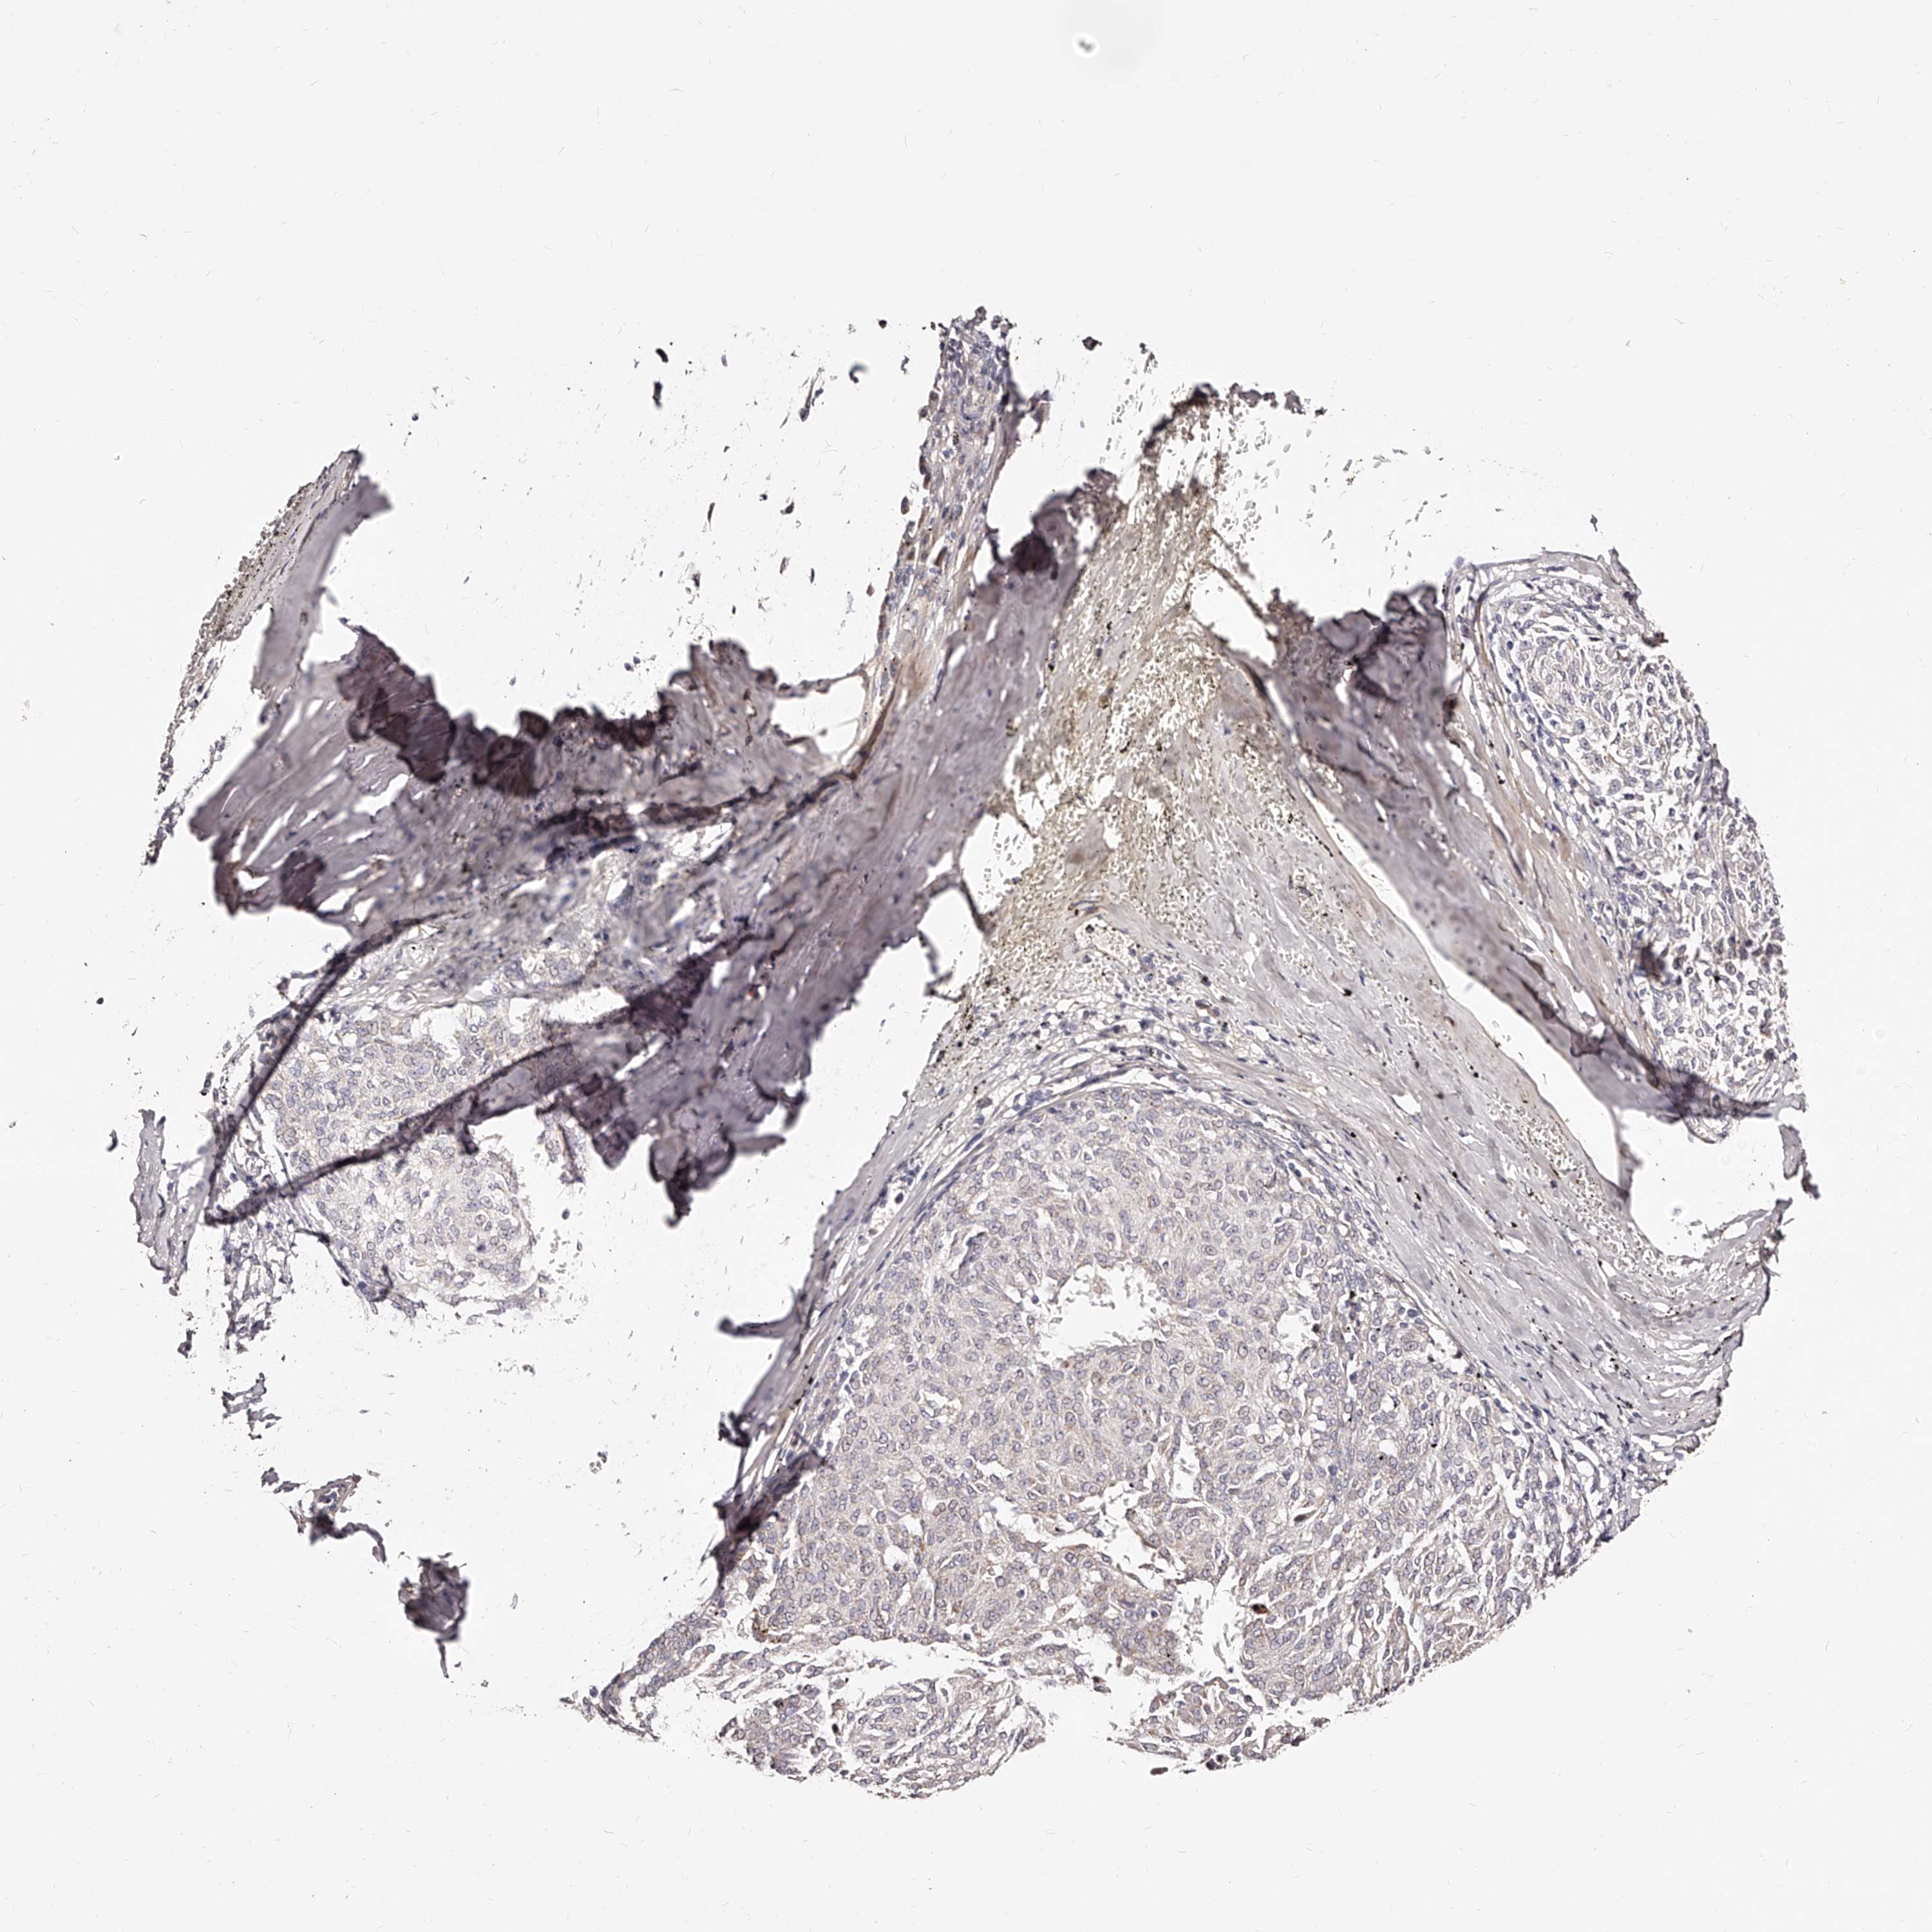

MELANOMA - Protein expressioni

A mouse-over function shows sample information and annotation data. Click on an image to view it in a full screen mode. Samples can be filtered based on level of antibody staining by selecting one or several of the following categories: high, medium, low and not detected. The assay and annotation is described here.

Note that samples used for immunohistochemistry by the Human Protein Atlas do not correspond to samples in the TCGA dataset.

Antibody stainingi

Antibody staining in the annotated cell types in the current human tissue is reported as not detected, low, medium, or high, based on conventional immunohistochemistry profiling in selected tissues. This score is based on the combination of the staining intensity and fraction of stained cells.

Each image is clickable and will lead to virtual microscopy that enables deeper exploration of all samples and also displays staining intensity scores, fraction scores and subcellular localization as well as patient and tissue information for each sample.

Antibody HPA024761

Antibody HPA029557

Staining

High

Medium

Low

Not detected

Intensity

Strong

Moderate

Weak

Negative

Quantity

>75%

75%-25%

<25%

None

Location

Nuclear

Cytoplasmic/membranous

Cytoplasmic/membranous,nuclear

Malignant melanoma, Metastatic site